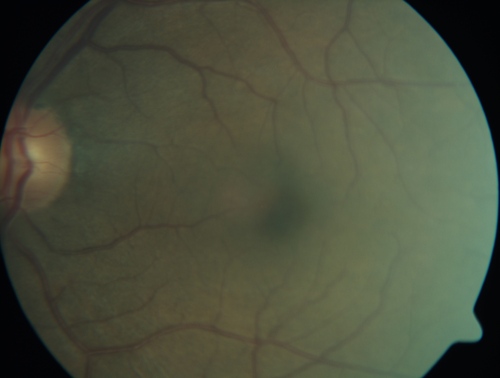

Macroaneurysm - Macular Hemorrhage - Branch Retinal Aterial Occlusion

62 year old African American female with chronic hypertension and vision loss for 2 weeks. VA is 20/400

Macroaneurym - Fresh Macular Hemorrhage - branch retinal arterial occulsion distal to MA